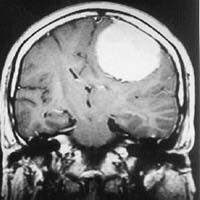

<ÃøµÎºÎ

³ú¼ö¸·Á¾>

<½Ã¼ú

Àü> <½Ã¼ú

ÈÄ>

¿ìÃø

Æí¸¶ºñ¸¦ ÁÖ¼Ò·Î ³»¿øÇÑ È¯ÀÚÀÇ ³úMRI¼Ò°ß

¹× ³úÇ÷°üÃÔ¿µ¼ú ¹× Ç÷°üÆó»ö¼ú¼Ò°ß